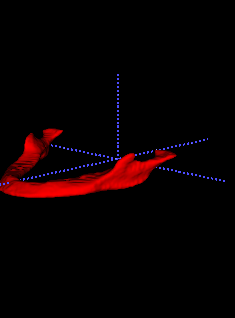

In Chapter 6, we propose an end-to-end, atlas-free 3D convolutional deep learning framework for fast and fully automated whole-volume HaN anatomy segmentation [115]. Our deep learning model, called AnatomyNet, segments OARs from head and neck CT images in an end-to-end fashion, receiving whole-volume HaN CT images as input and generating masks of all OARs of interest in one shot. AnatomyNet is built upon the popular 3D U-net architecture, but extends it in three important ways: 1) a new encoding scheme to allow auto-segmentation on whole-volume CT images instead of local patches or subsets of slices, 2) incorporating 3D squeeze-and-excitation residual blocks in encoding layers for better feature representation, and 3) a new loss function combining Dice scores and focal loss to facilitate the training of the neural model. These features are designed to address two main challenges in deep-learning-based HaN segmentation: a) segmenting small anatomies (i.e., optic chiasm and optic nerves) occupying only a few slices, and b) training with inconsistent data annotations with missing ground truth for some anatomical structures. We collect 261 HaN CT images to train AnatomyNet, and use MICCAI Head and Neck Auto Segmentation Challenge 2015 as a benchmark dataset to evaluate the performance of AnatomyNet. The objective is to segment nine anatomies: brain stem, chiasm, mandible, optic nerve left, optic nerve right, parotid gland left, parotid gland right, submandibular gland left, and submandibular gland right. Compared to previous state-of-the-art results from the MICCAI 2015 competition, AnatomyNet increases Dice similarity coefficient by 3.3% on average. AnatomyNet takes about 0.12 seconds to fully segment a head and neck CT image of dimension , significantly faster than previous methods. In addition, the model is able to process whole-volume CT images and delineate all OARs in one pass, requiring little pre- or post-processing. We demonstrate that our proposed model can improve segmentation accuracy and simplify the auto-segmentation pipeline. These contributions are released as an open-source software package called AnatomyNet, which is publicly available555https://github.com/wentaozhu/AnatomyNet-for-anatomical-segmentation. Portions of this chapter were published as part of [115].

- [121] W. Zhu and X. Xie. Adversarial deep structural networks for mammographic mass segmentation. arXiv:1612.05970, 2016.